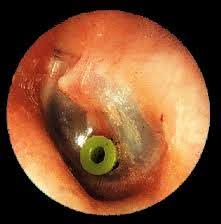

ΤΥΜΠΑΝΟΠΛΑΣΤΙΚΗ – ΟΣΤΑΡΙΟΠΛΑΣΤΙΚΗ

ΜΥΡΙΓΓΟΤΟΜΗ – ΣΩΛΗΝΙΣΚΟΙ ΑΕΡΙΣΜΟΥ